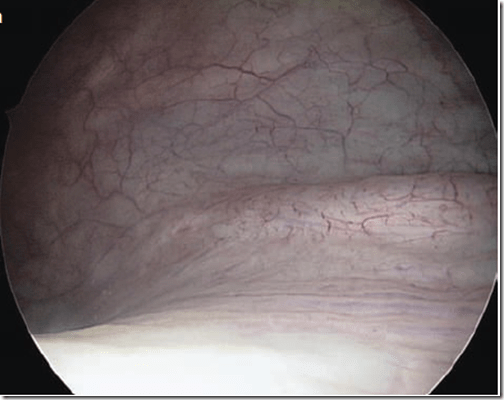

Imagen: Se aprecia el interior de la vejiga a través de un cistoscopio. Atlas of Urogynecological Endoscopy. Peter L. Dwyer, 2007

La cistoscopía es un procedimiento mediante el cual se visualiza el interior de la uretra y la vejiga a través de un instrumento óptico llamado cistoscopio. Cuando usted tiene un problema en la vejiga se puede emplear un cistoscopio para examinar el interior de la vejiga y uretra (tubo que conduce la orina desde la vejiga hasta su salida fuera del cuerpo).

Se puede realizar una cistoscopía para ayudar a confirmar un diagnóstico o establecer la causa de síntomas como: Sangre en la orina (hematuria); presencia de células atípicas en orina; infecciones urinarias frecuentes; dolor en la vejiga y la uretra durante la micción; durante procedimientos quirúrgicos como histerectomía o en aquellos para la cura de incontinencia, donde se confirma que no hay lesión de la vejiga o los uréteres. La cistoscopía es un procedimiento muy útil en el diagnóstico de cálculos vesicales, tumores sangrantes, malformaciones vesicales.